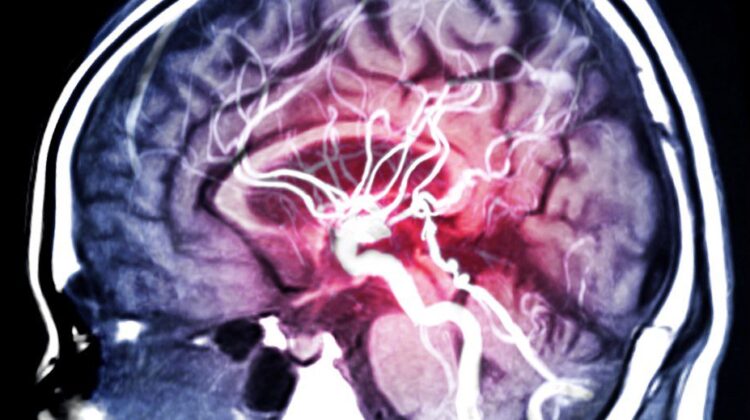

“Do not ignore this… read it in full!” This isn’t just a catchy phrase to grab your attention; it is a genuine call for awareness about a condition often known as the “silent killer.” An aneurysm is a bulge or ballooning in the wall of an artery. If left undiagnosed, it can rupture, causing life-threatening internal bleeding in a matter of moments.

1. Ruptured Brain Aneurysm

- The worst headache of your life: Medically described as a “thunderclap” headache, this is a sudden, severely intense pain that feels completely different from any headache you have ever experienced.

- Nausea and vomiting: Often accompany the intense, blinding headache.

- Stiff neck: Noticeable pain or stiffness that makes it difficult to move your neck freely.

- Vision problems: This can include blurred or double vision, extreme sensitivity to light, or a drooping eyelid.

- Severe neurological changes: Such as sudden confusion, loss of consciousness, weakness or numbness on one side of the face, or even a seizure.

- Dilated pupils: One or both pupils may become abnormally enlarged.